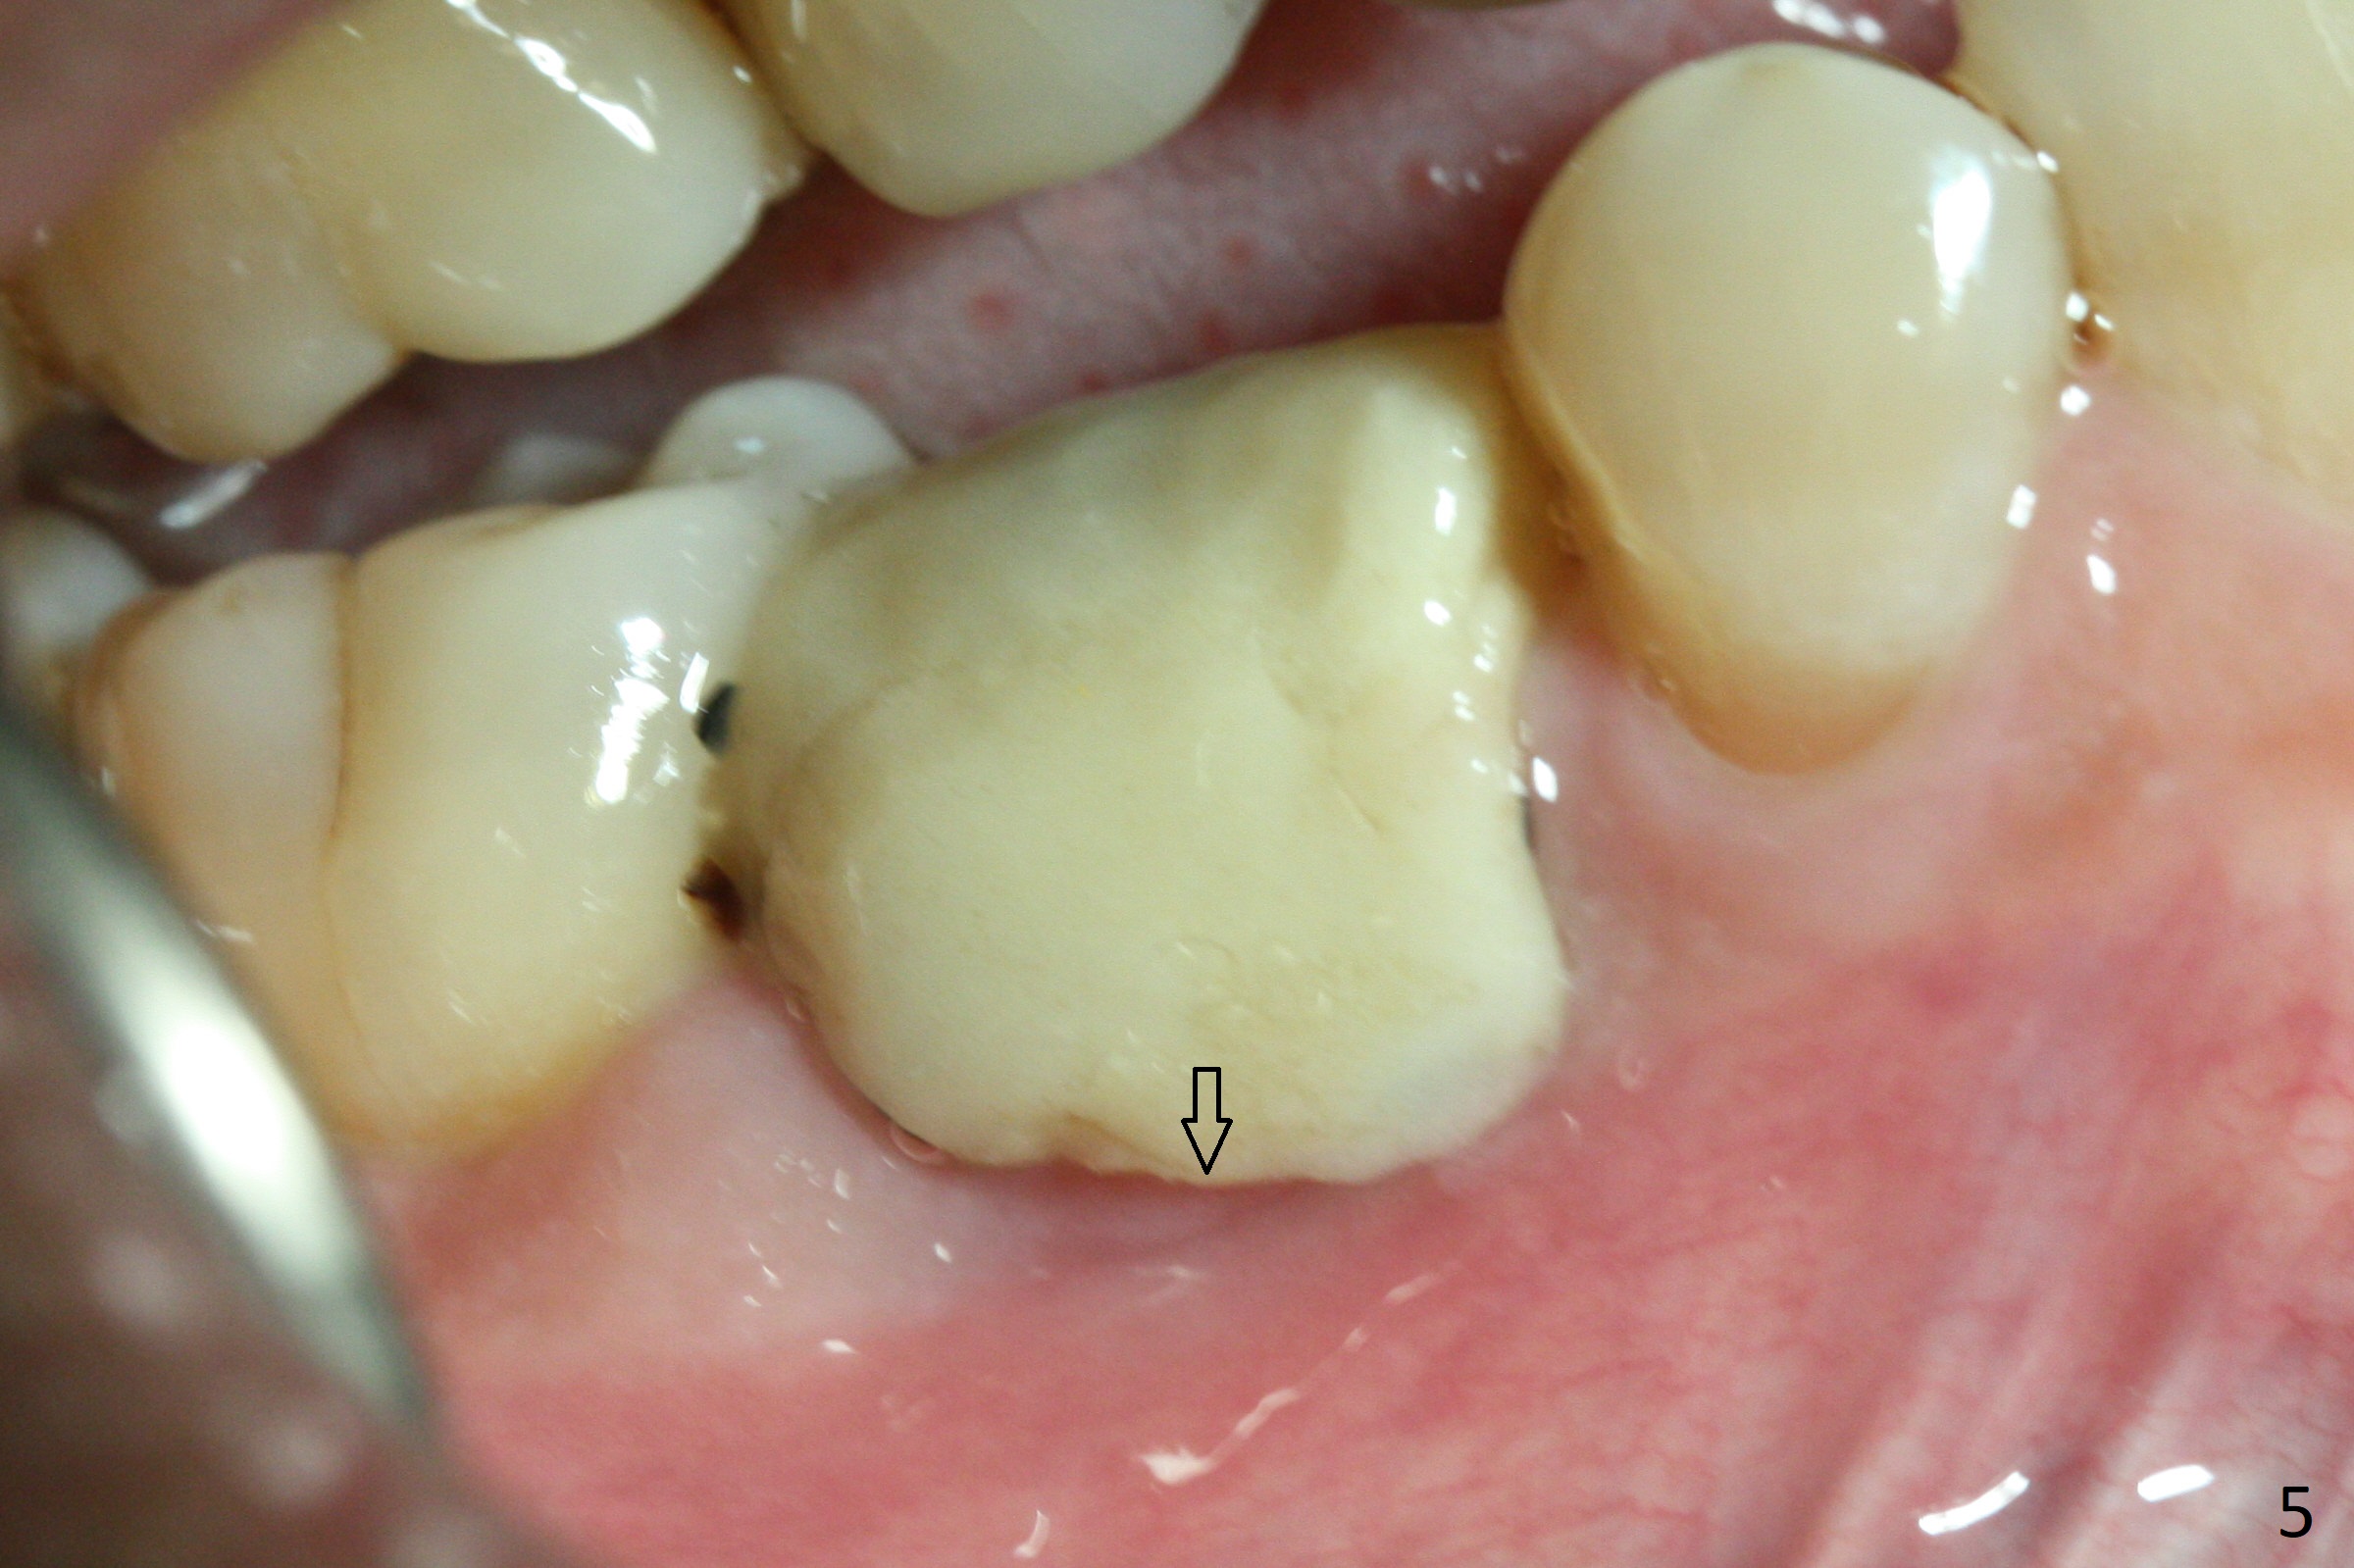

The retained deciduous tooth (lower right 2nd molar, Fig.1 T) has buccal apical infection and recession. After extraction, the initial depth of osteotomy is 11 mm over the flat socket bottom (Fig.2) without visible Mental Loop. Following 3.8 mm Magic Drill for 11 mm, a 4x11 mm dummy implant is placed partially due to hard bone; it appears that the apical osteotomy (Fig.3 yellow outline) overlaps the Mental Loop (red dashed line). For safety, a 4x9 mm IBS implant is placed with insertion torque 40 Ncm; a 5x5.7(4) mm abutment is immediately placed for an immediate provisional to cover the large socket and keep Vera graft in place (Fig.4 *). There is no postop paresthesia, probably due to the fact that the osteotomy is lingual to the Mental Loop. The provisional remains in place 7 days postop; its margin (Fig.5 arrow) covers the socket. The margin of the provisional is trimmed 1 month postop. Impression is taken nearly 3 months postop (Fig.6). The buccal plate looks atrophic 3 months postop (Fig.7 (immediately before cementation)), although there is no sign of periimplantitis. In the future, insert the immediate provisional inside of the buccal gingiva to make the buccal gingiva look bulky instead of buccal to it (Fig.5). The second drawback of placing an implant at the deciduous tooth area is that the crown is wide mesiodistally if orthodontic treatment is not rendered. Although there is lower anterior crowding, the patient declines orthodontic treatment. The bone density around the implant increases 7 months post cementation (Fig.8 *). The higher density bone seems to extend coronally 1 year 7 months post cementation (Fig.9). The dense bone apparently extends toward the abutment as well 3 years 5 months post cementation (Fig.10 curved arrows).